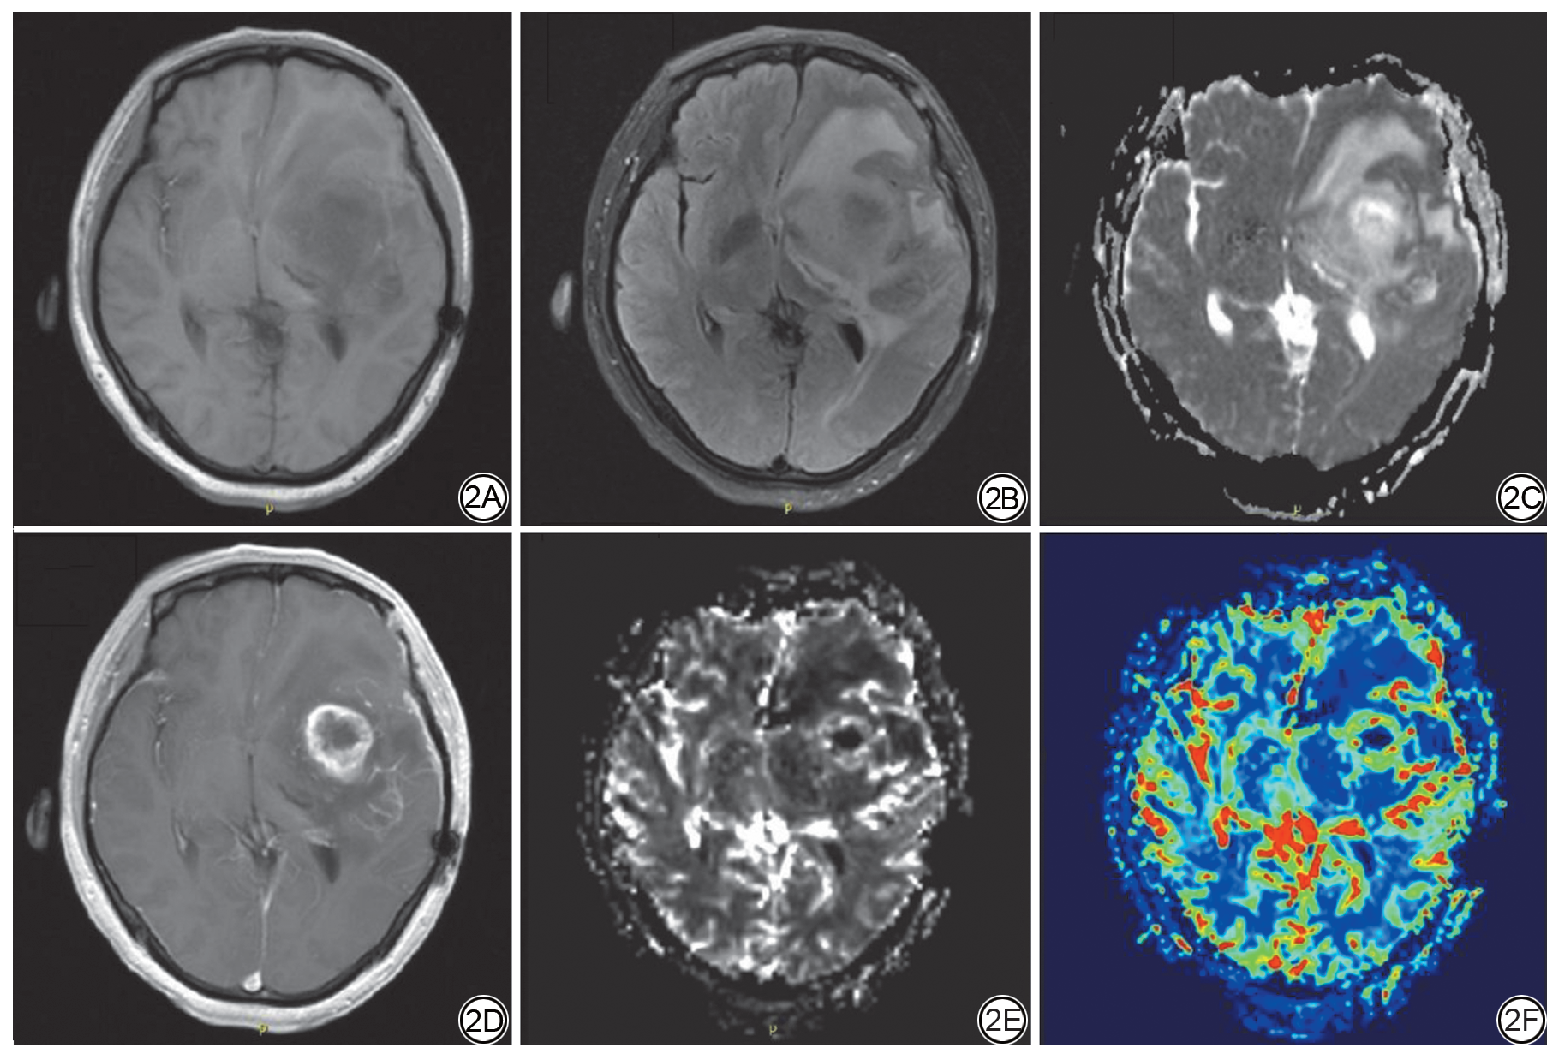

首先使用MATLAB软件对图像进行配准,将所有患者的ADC、CBV图像配准到CE-T1WI图像。随后由一名放射科住院医师(具有2年神经影像诊断经验)参考CE-T1WI图像及FLAIR图像,使用MRIcroGL软件在CE-T1WI图像上勾画病灶强化区作为感兴趣区(volume of interest, VOI),在勾画过程中避开囊变、坏死或出血区域,并且为了减小部分容积效应,每层的VOI要稍小于实际病灶的大小,同时在FLAIR图像上勾画瘤周2 cm范围内的水肿区,分别测量异常强化实质区域及瘤周水肿区域的CBV、ADC值及对侧半卵圆区域CBV值。平均相对CBV(relative CBV, rCBV)为病灶强化区CBV值与对侧半卵圆区域平均CBV值的比值[23, 24, 25]。最后所有图像均由一名资深神经放射科主任医师(具有20年神经影像诊断经验)进行确认。VOI勾画示意图如图1所示。

图1  感兴趣区勾画示意图。红色感兴趣区表示病灶强化区,绿色感兴趣区表示瘤周水肿区。

Fig. 1  Schematic diagram of volume of interest (VOI) delineation. The red VOI represents the contrast-enhancing lesion; The green VOI represents the peritumoral edema region.